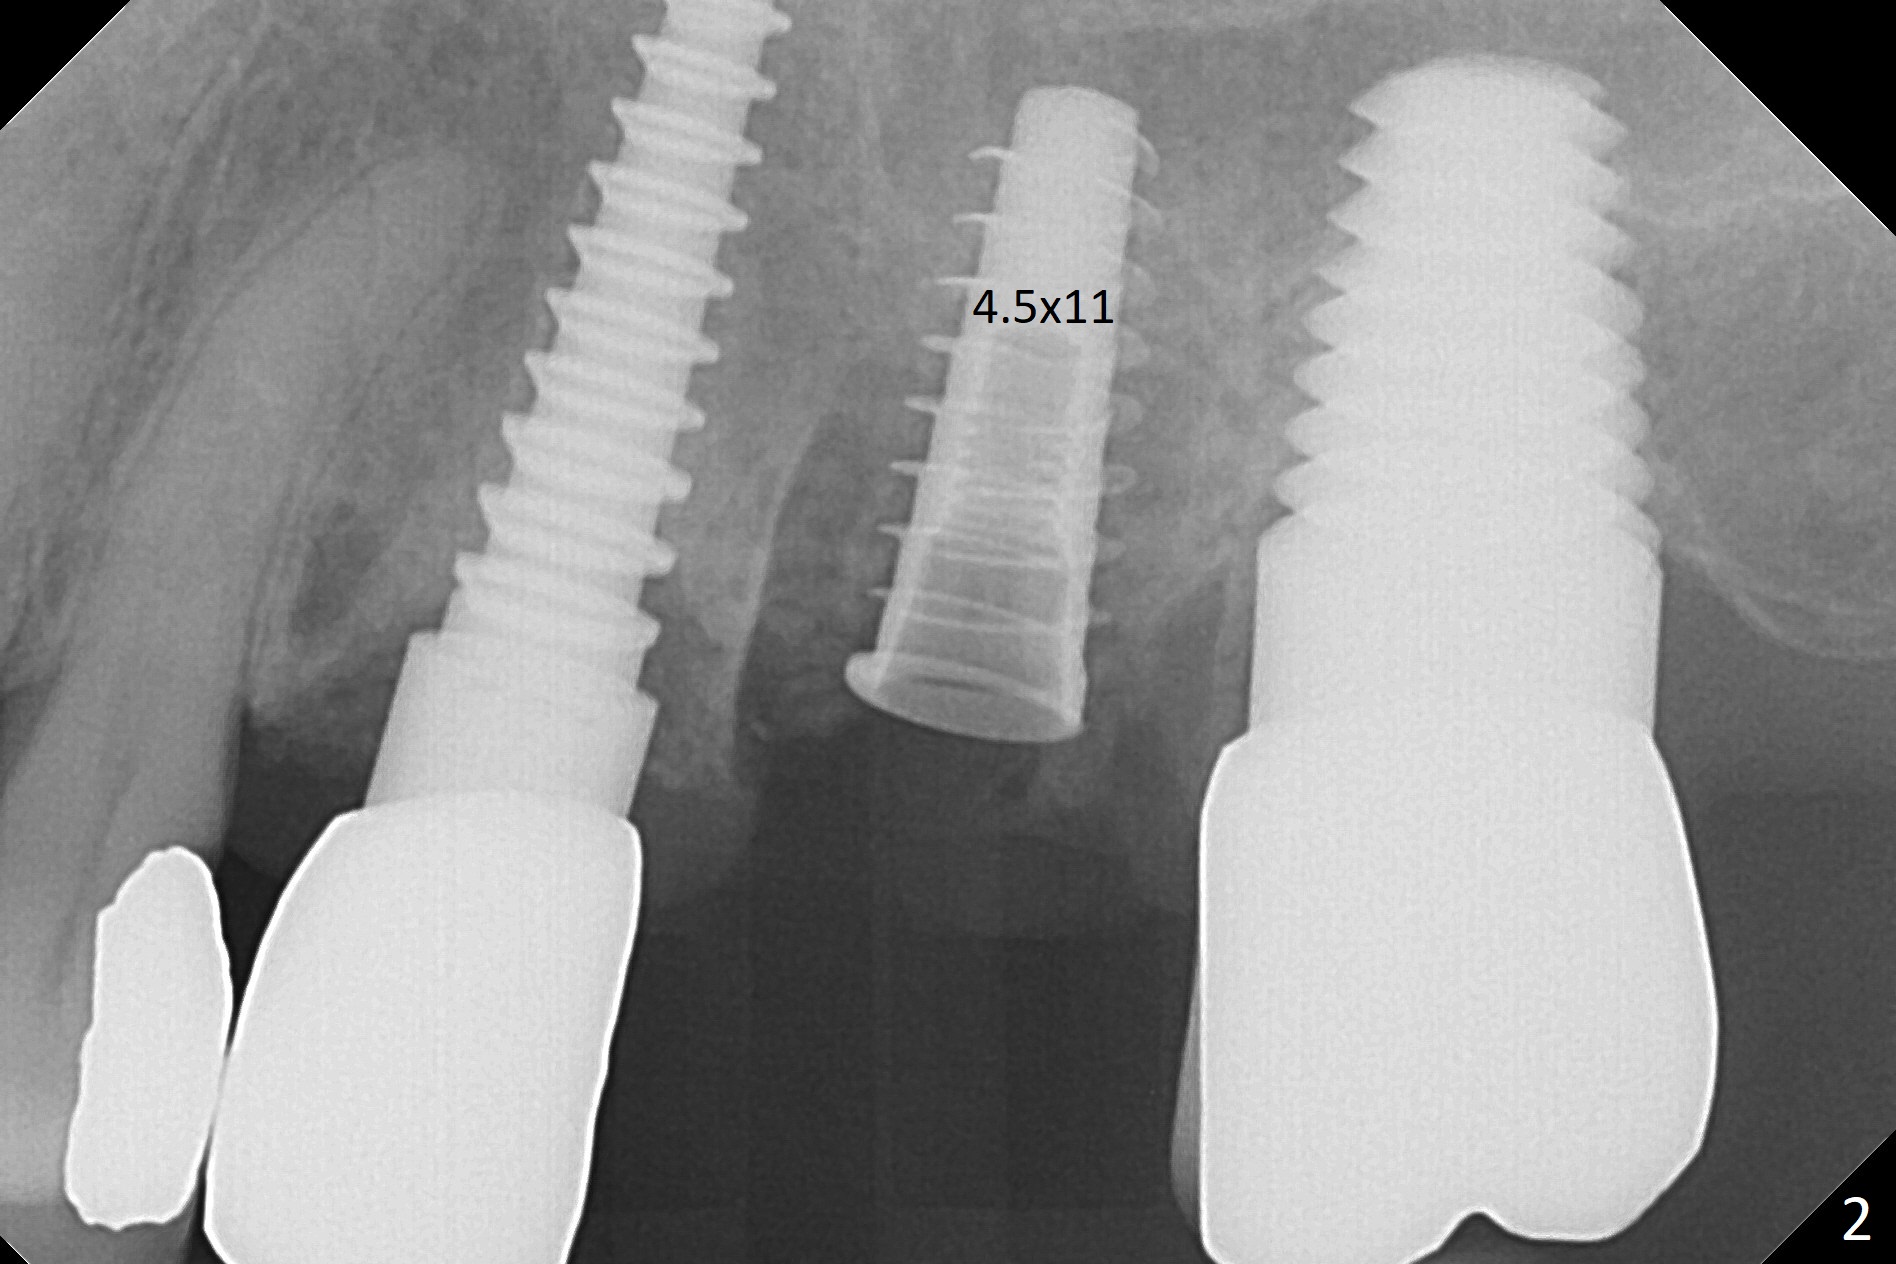

Initial osteotomy in the septum of the tooth #14 is 9 mm, approximately 2 mm from the sinus floor (Fig.1). Subsequent osteotomy depth is 11 mm, followed by insertion of a 4.5x11 mm dummy implant (Fig.2). After use of Magic Drill (MD) 4.8 mm for 9 mm, a 5x11 mm IBS implant is placed with sinus lift without additional bone graft (Fig.3 *). In contrast, autogenous bone (from MD) and Vanilla Graft are meticulously placed in the remaining socket (+) before and after placement of a 6.5x5.7(2) mm abutment. An immediate provisional is fabricated to close the sockets. There is buccal tenderness 1-3 months postop. There is distopalatal implant thread exposure. A healing abutment (5.5x2 mm) is placed. CT confirms thin buccal plate (Fig.4,5). It appears that the implant should have been as palatal as possible. The tenderness remains for the next 2 weeks. When the healing abutment is removed, the implant seems to have been placed shallow, ~ 1 mm subgingival (Fig.6). With local anesthesia, the implant is reversed to clean the coronal threads with Titanium brush and copious irrigation (Fig.7). The implant is then placed ~4 mm subgingival (Fig.8) and slightly subcrestal (Fig.9,10). It appears that the postop bone loss (Fig.9 *, as compared Fig.1,2) makes the implant look to be placed too shallow. When the implant is being placed deeper, the buccal plate feels intact. The early periimplantitis is apparently due to postop bone loss more than buccal placement, although certain degree of buccal bone resorption must occur. A 6x4 mm healing abutment is placed. Left facial swelling develops 2 days post implant elevation (Fig.11,12, as compared to preop (Fig.13)). The left maxillary sinus cloud (Fig.12) appears to be a false positive finding, since the same feature exists prior to implant elevation (Fig.13). Both sinuses look clear prior to implant elevation (Fig.14). Amoxicillin switches to Augmentin and Flagyl, since the patient is reluctant to have the implant removed. Finally the sinus infection is under control. The patient feels left facial swelling 9 months postop (5 months post elevation) and reports left nasal discharge ~ 1 month earlier. There is mild buccal plate tenderness. The implant seems to be buccally placed (Fig.15,16), although there is no significant change radiographically (Fig.17). The implant is removed with bone graft (Fig.18 *). To avoid complication and failure, an immediate implant at the upper 1st molar should be short and placed deep.